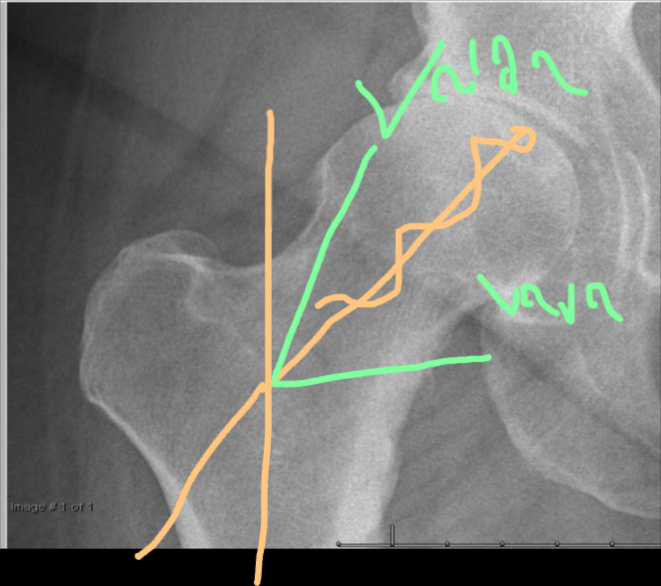

AP HIP Joint line narrowing, osteophyte formation, subchondral sclerosis and cysts, no obvious deformity

Five Key Features

- Narrowing of the joint line

- Formation of osteophyte

- Subchondral sclerosis

- Subchondral cyst

- Joint deformity

X-ray AP Lateral Osteophyte formation - joint space narrowing - Subchondral cyst adn sclerosis - joint Varus deformity